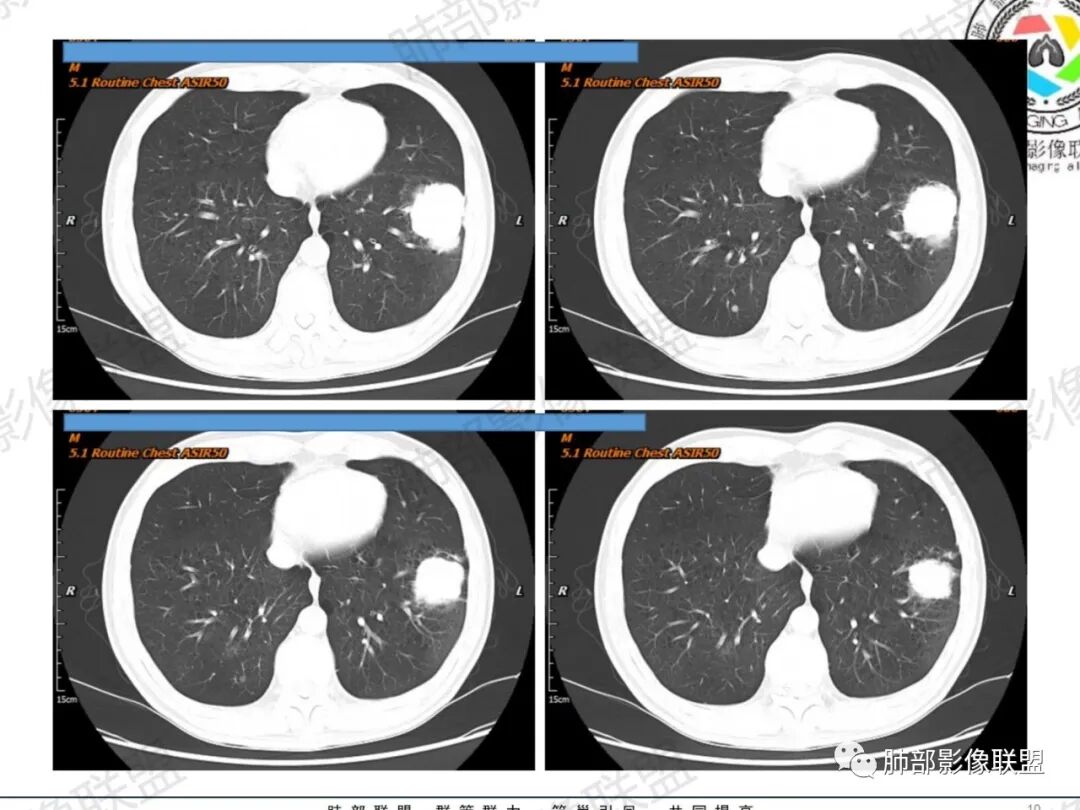

一切∮随缘:左肺下叶不规则肿块,边缘光滑,平直,局部彭隆,分叶,近端支气管堵塞,远端与胸膜相贴,平扫密度尚均匀,增强后不均匀强化,内部可见低密度坏死,胸膜下多发肺气肿,伴双肺散在光滑小结节,实验室肿瘤标志物高,考虑恶性:神经内分泌癌(大细胞),腺癌,鳞癌。

琦遇:恶性没有问题,肺气肿底子、病灶分叶、少许毛刺、叶间胸膜凹陷、部分边缘可见清晰的GGO、胸膜牵拉凹陷、局部胸水、近端支气管截断、部分支气管被推移、占位效应明显、强化特点为不均匀强化、内部有少许沼泽样低强化区,强化部分轻中强化为主、余肺可见转移性结节、左肺上叶似为囊腔型腺癌一枚,肿瘤标志物提示非小、神经内分泌,综合分析考虑大神泌、腺癌、腺鳞癌、鳞癌  同时左肺上叶囊腔型腺癌  肺转移

飞鹰行动:中年人,男性,胸疼入院,左肺下叶占位,张力较高,边界可见分叶,局部可见明显收缩性改变,增强病灶内部有延迟强化表现,考虑恶性病变,大细胞癌伴肺内转移或者囊腔样腺癌伴转移。

蕊:中老年男性,吸烟史,肺气肿背景,左肺上叶类圆形肿块影,边界清晰,边缘凹凸不平,有分叶,支气管进入阻断,临近胸膜栽赃,整体病灶膨隆,局部周围可以清晰ggo,临近叶间裂内凹,轻度强化,并可见多个低密度区,坏死可能,界线不清;肺内多结节,边缘光滑,考虑恶性伴转移,鳞癌、腺癌

傅昌瑜:中老年男性,肺气肿背景,右胸背疼痛1周。CEA、NSE、CYFRA—211升高。左上肺混合磨玻璃结节,内见较多空泡和扩张支气管。左下肺胸膜下肿块,边缘较光滑,深分叶,似有血管进入,与支气管关系不清,内见不均匀强化,见沼泽地样坏死,有胸膜栽赃。另两肺多发圆形小结节。考虑恶性并肺内转移,多原发可能性大,左上肺腺癌,左下肺病理难以判断,小细胞癌?鳞癌?

小锁:中老年男性,肺气肿背景,右胸背疼痛1周。CEA、NSE、CYFRA—211升高。左上肺混合磨玻璃结节,边界清楚,内见较多空泡。左下肺肿块,边缘清楚,深分叶,有血管和支气管进入,胸膜凹陷。另两肺多发圆形小结节。考虑双发原位癌,左上肺腺癌,左下肺大神泌或腺鳞癌可能,肺内转移。

蓝天白云:中年男性,肺气肿背景,左肺下叶肿块,边缘膨隆,有分叶,内有湖泊样坏死,有轻中度强化,局部胸膜栽赃,收缩力不强,周围见肺气肿征象。左肺上叶混合磨玻璃影,边界清楚,考虑都是恶性,左上肺iac,左下肺腺鳞癌,或大细胞肺癌可能。两肺多发结节,考虑转移

毛勤香:老年男性,肺气肿背景,左肺下叶肿块,分叶,边缘光滑,土豆块样,细支气管闭塞,增强轻度不均匀强化,似有坏死,左肺另见多发结节,淋巴结未见明显肿大,恶性确定,吸烟史,鳞癌破坏力强,侵袭力差,多原发的一般很少多于3个,故排后,首先考虑神经内分泌癌,局部血管穿行,鉴别淋巴瘤

周太狼:中年男性,吸烟、高血压史,肿瘤指标升高,肺气肿背景下,左肺下叶肿块影,分叶、膨隆、未跨叶裂,支气管截断,不均匀强化。另双肺多发结节及磨玻璃影,左肺上叶混合磨玻璃,内可见多发空泡影。整体考虑恶性,肺癌伴肺内转移,左下肺鳞癌?神经内分泌癌?左肺上叶囊腔腺癌?